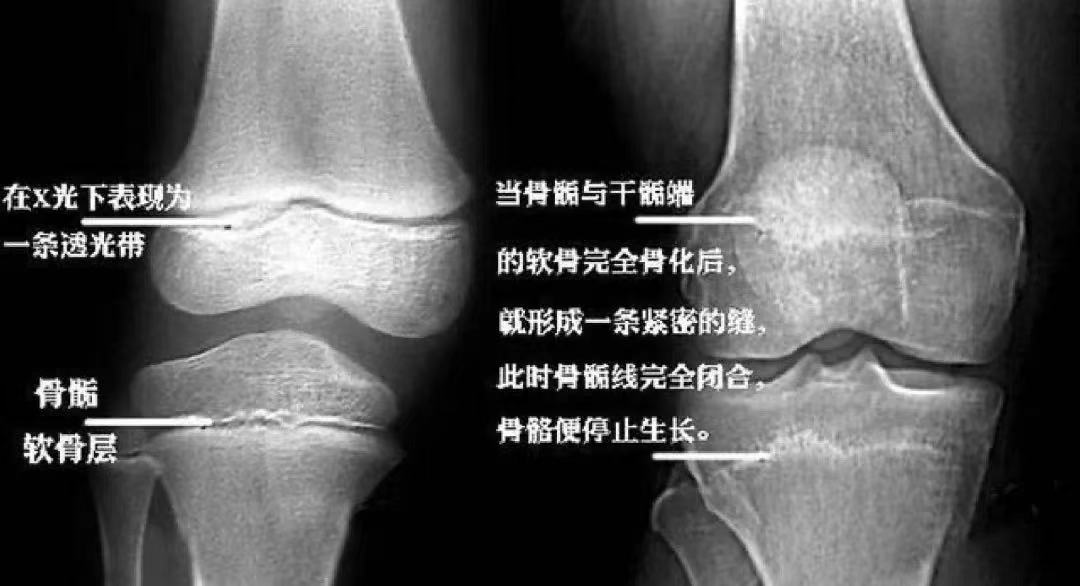

案 例 16岁的男孩小杨身高才156厘米,而且父母发现小杨今年身高没什么变化,好像已经停止生长了,赶紧带着他来看医生。 经过骨龄检查,结果显示小杨骨龄已经18岁了,比实际年龄早了2岁,再也没有长高的机会。即便注射生长激素进行干预,但根据骨龄预测小杨的成年终身高很有可能达不到1米6,因为他已经错过最佳的生长干预期。诊断结果让小杨父母追悔莫及。 ▲小杨的骨干骺端接近闭合 骨龄,决定着生长空间 骨龄就像车上的汽油,用一点少一点。 骨龄跑的慢,油耗低,跑得远跑的长; 骨龄跑得快,油耗高,跑得近跑得短。 我们看下还有生长空间的孩子生长板是什么样的: ▲左图为4.7岁孩子的生长板,清晰可见 右图为17岁男孩,骨干骺端完全闭合,生长板消失 ▲膝关节X光片 通过小杨的案例, 我们可以得到下面两个重要结论: 一、定期监测骨龄,评估生长发育情况 为什么医生总是提醒家长,孩子应该从3岁开始定期监测骨龄? 定期监测骨龄,能够及时地评估孩子的生长发育情况,预测孩子还能长多高,成年终身高是多少,医生也可以因此制定相应的身高管理方案,帮助孩子达到理想身高。 骨龄检测(3-15岁), 预测成年终身高、判断发展潜力 售价258元, 点击下图即可了解详情~ 点击↓↓↓ 二、生长期要抓牢,身高管理要尽早 一个人身高的80%是在青春期之前完成的,越小进行身高管理,骨干骺端距离闭合的时间越长,干预的方法也越多。每早一年干预,孩子就可能多长1-2cm,越容易达到期望身高。 越晚进行身高管理,不仅干预的方法少,花费也更高,达到期望身高的难度也更大。 科学长高管理(3-14岁), 定制管理计划,特色管理方案, 仅需1280元/年! 点击下图即可了解详情~ 点击↓↓↓ 最后,提醒各位家长朋友,如果孩子的身高一直不理想或者想要孩子长到期望身高,就应该尽早地做身高检查,评估生长发育情况,尽早干预,做好身高管理,定期监测骨龄。